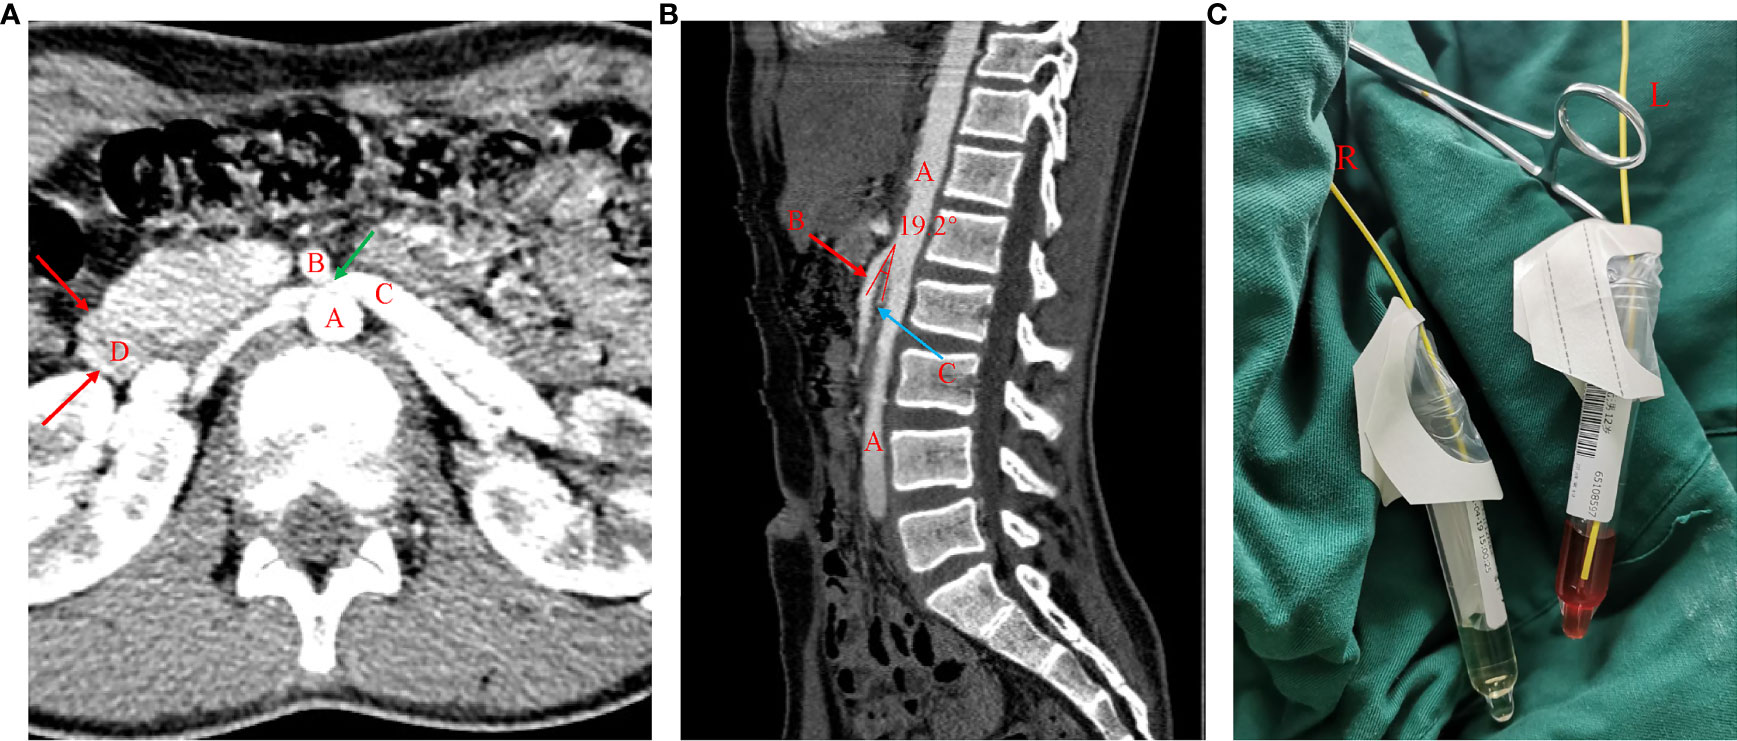

Frontiers Case Report An Unusual Case of Nutcracker Syndrome and

Frontiers Case Report An Unusual Case of Nutcracker Syndrome and Nutcracker Disease Usmle The management of this uncommon disease process poses a challenge for adequate recommendations of the best treatment modality. Nutcracker phenomenon refers to compression of the left renal vein, most commonly between the. Nutcracker phenomenon refers to compression of the left renal vein, most commonly between the aorta and the superior mesenteric artery, with impaired blood outflow often accompanied by distention. Nutcracker Disease Usmle.